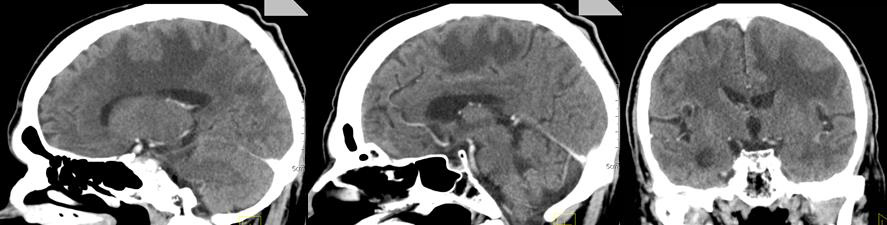

Three months after WBRT, the patient complained of difficulty in balance and weakness of the right limbs. CT of brain with venous contrast - Parenchymal brain pathology is not visualized subtentorially. Edema zones temporoparietally and occipitally in the left cerebellar hemisphere, without visible nuclei of metastases are reported. Ventricular system and basal cisterns - undilated, without dislocation. Mild cortical atrophy bilaterally temporally is visualized (Figure 3).

Figure 3: CT of the brain after 3 months of prophylactic WBRT - Edematous areas temporoparietally and occipitally in the left cerebral hemisphere.

Prophylactic whole-brain radiotherapy (PWBRT)

The whole-brain radiotherapy (WBRT) is conducted for two therapeutic purposes - preventive or prophylactic and curative. PWBRT is a standard approach in the limited or advanced stage of small cell lung cancer (SCLC) in clinical remission after systemic chemotherapy (Ch) and local pulmonary radiotherapy (RT). Without PWBRT, 60% of SCLCs develop brain metastases (BM), and they are reduced to 20% after it was performed [10]. PWBRT is also recommended for non- small cell lung cancer (NSCLC) [11-15], in which a significant reduction in BM of 18% to 8% without improved overall survival (OS) has been achieved [16] in contrast to SCLC, where OS is significantly increased [17,18]. The purpose of PWBRT is to destroy microscopic metastatic tumor cells in the brain before their clinical manifestation. Radiation brain effects after PWBRT are divided into acute, subacute and chronic [19]. Acute side effects occur during or one to two weeks after completion of PWBRT. They are expressed by general fatigue, alopecia and symptoms associated with increased cerebral edema - headache, nausea, focal brain deficits, a pronounced mental change [20]. These acute symptoms gradually subside in a large proportion of patients. On MRI, diffuse cerebral edema is visualized [21]. Subacute symptoms develop immediately after the completion of RT or three months after its completion. They are relatively rare and limited, mainly to drowsiness syndrome and less commonly as leukoencephalopathy [20]. 3 months after 10x3Gy PWBRT, the condition of a 73-yearold SCLC patient, who underwent 6 courses of Ch (Cisplatin and Etoposide) deteriorated. CT and MRI visualize extensive cerebral edema in the left hemisphere, without brain metastases (Figure 3 & 4). In children with leukemia after PWBRT, there is a “radiation somnolence syndrome” characterized by somnolence often associated with headache, nausea, vomiting and sometimes fever. The necessary treatment is the administration of corticosteroids, but it should be noted that these complaints may resolve spontaneously [22]. Somnolence is more common in children with PWBRT with concomitant chemotherapy (methotrexate/ intrathecal) [23]. Pathophysiologically, this somnolent syndrome is associated with transient demyelination of the white matter. On the other hand, it should be noted that leukoencephalopathy is considered a more severe manifestation of demyelination and may be fatal. These changes in white matter are much more common in adult patients with concomitant chronic cerebrovascular ischemia [20]. Symptoms are usually mild and stabilize or resolve. Imaging - CT and MRI with intravenous contrast varies from diffuse cerebral edema to increased accumulation of contrast [21]. In the presented adult patient it can be seen that against the background of antiedema medication treatment (Dexamethasone and Mannitol), the symptoms was not transient, on the contrary, they worsen (Figure 3 & 4). Subacute encephalopathy usually begins two or three months after cerebral RT but may occur 2 weeks to 4 months after completion of PWBRT. It is usually seen in patients with SCLC after chemotherapy of the primary tumor. The pathogenesis of subacute encephalopathy is due to demyelination due to damage to the oligodendroglia with subsequent involvement of the myelin sheaths [22]. The progression of these changes leads to late effects manifested by radionecrosis [23-25]. Tissue necrosis is a distinct syndrome of radiation toxicity, thought to be the consequence of vascular endothelial cell damage, resulting in fibrinoid necrosis of small vessels and direct brain parenchymal necrosis. Occlusion of small blood vessels results in focal coagulative necrosis, capillary leakage, and demyelination of the surrounding brain parenchyma [26,27]. The relationship between PWBRT and late brain toxicity was analyzed in 264 patients with limited stage SCLC [28]. Patients are divided into 3 arms depending on the DD and the TD: 10 fractions up to TD 25 Gy; 18 fractions up to TD 36 Gy and hyperfractionated RT ( two daily fractions) with 24 fractions up to TD 36 Gy. Neurological changes are reported after 6 months and 12 months of PWBRT. After 1 year, neurotoxicity was established in 60% of patients after TD 25 Gy and in 80-90% after TDs 36 Gy.